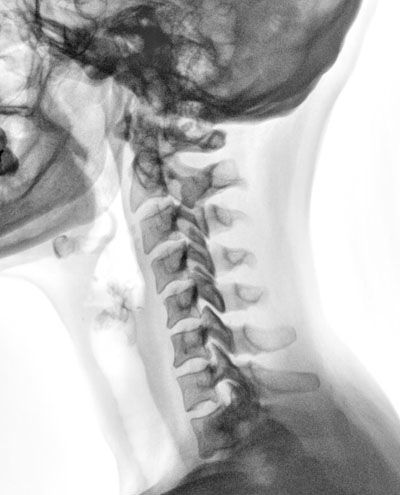

Le fait de passer de nombreuses radiographies est-il dangereux ? Publié le 23/05/2011, mis à jour le 24/05/2011 par SFR Rappelons tout d’abord que les radiographies ont recours aux rayons X. Les rayons X sont des rayonnements ionisants invisibles capables de traverser le corps humain qui les arrête partiellement. Cette atténuation du rayonnement provoquée par les différents composants du corps humain (os, graisse, muscles, eau, air, vaisseaux…) permet en radiologie de réaliser une image diagnostique. Les rayonnements ionisants à fortes doses peuvent provoquer des effets secondaires bien connus comme «les radiodermites». Ces fortes doses ne sont pas atteintes dans le cadre de l’imagerie diagnostique. En revanche, les effets secondaires des faibles doses sont beaucoup moins connus, en particulier l’apparition de mutations génétiques et de cancer, car ils peuvent survenir bien après l’exposition et ne se distinguent pas des affections naturelles. Il n’existe cependant aucune preuve que les examens d’imagerie diagnostique puissent être à l’origine de cancers. En raison de cette incertitude, les organismes internationaux et nationaux utilisent le «principe de précaution» pour établir la réglementation, comme s’il existait, même à faibles doses, une relation linéaire entre la dose et le risque. Quand le bénéfice est supérieur au risque Pour comprendre la complexité du problème, il faut savoir que l’imagerie médicale n’est pas la seule source d’exposition aux rayonnements ionisants. Nous sommes exposés quotidiennement à de faibles doses de rayonnements ionisants qui proviennent de nombreuses sources : de l’air que nous respirons, des sols, des rayonnements cosmiques, des matériaux de construction, de l’eau, des aliments… Cette exposition aux rayonnements ionisants d’origine naturelle est estimée en moyenne en France à 2,5 millisieverts (mSv) par an. En comparaison, une radiographie de thorax délivre entre 0,005 et 0,01 mSv soit l’équivalent d’un à deux jours d’exposition aux rayonnements ionisants naturels. Une radiographie de l’abdomen délivre environ 0,4 mSv soit près de deux mois d’exposition aux rayonnements naturels. Un lavement baryté environ 2,5 mSv soit une année d’exposition aux rayonnements naturels. Une tomodensitométrie du crâne environ 2 mSv soit 10 mois d’exposition aux rayonnements naturels. Une tomodensitométrie de l’abdomen de 5 à 10 mSv soit deux à quatre ans d’exposition aux rayonnements naturels. La radioprotection désigne l’ensemble des mesures prises pour assurer la protection de l’homme et de son environnement contre les effets néfastes des rayonnements ionisants. Tous les médecins radiologues et leurs collaborateurs bénéficient d’une formation initiale et continue obligatoire en radioprotection. Les deux grandes règles de radioprotection, justification et optimisation, sont mises en œuvre au quotidien par les professionnels. La justification réside dans le fait que, comme dans tout acte médical, le bénéfice doit être supérieur au risque. Bien que le risque des faibles doses ne soit pas démontré, la prudence veut que l’on considère sa possible responsabilité. Il faut donc que l’indication d’un examen exposant aux rayonnements ionisants soit bien réfléchie et pesée. Il appartient à votre médecin radiologue de valider l’indication de l’examen demandé par votre médecin, voire de proposer un autre examen permettant de répondre à la question qu’il se pose. Il est ainsi parfois possible de remplacer un examen utilisant des rayons X par un examen n’en utilisant pas, comme l’échographie ou l’imagerie par résonance magnétique (IRM). La Société française de radiologie a élaboré le guide du bon usage des examens d’imagerie pour permettre à tous les médecins de connaître l’examen répondant le mieux à la situation clinique de leur patient. L’optimisation des doses utilisées est la responsabilité des radiologues et des manipulateurs qui ont l’habitude d’utiliser le minimum de rayons nécessaires à l’obtention d’un examen permettant de répondre aux questions posées. Ces mesures sont prises pour tous les patients, mais sont encore renforcées pour les examens pratiqués chez les enfants dont la sensibilité aux rayonnements ionisants est plus grande et chez les patients porteurs d’une maladie chronique nécessitant des examens répétés. Si le risque des rayonnements ionisants ne doit pas être sous-estimé, il ne faudrait pas que la crainte d’effets secondaires jamais démontrés soit responsable d’une perte de chance pour les patients et fasse oublier les importants bénéfices apportés par l’imagerie aux malades. Grâce à ces examens, les radiologues réalisent des diagnostics rapides et précis qui permettent de traiter plus rapidement les patients et de suivre l’efficacité de leur traitement. Hubert Ducoulepointe; responsable du groupe radioprotection de la SFR